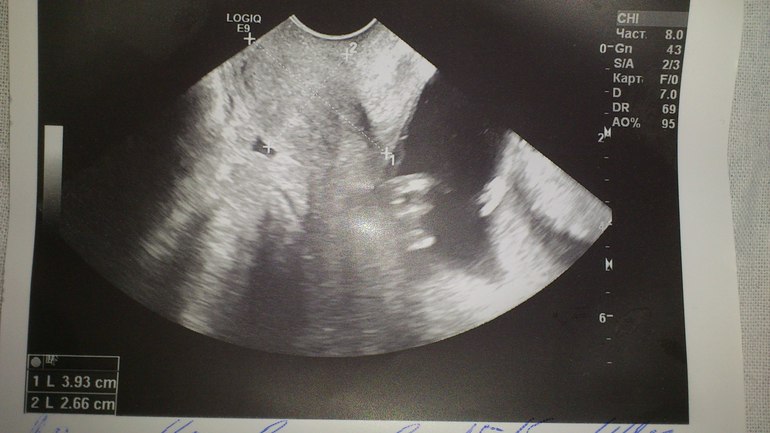

Расскажу, что у нас было за этот период. В начале Б. два раза лежала в больнице, первый раз с почками, второй раз с гематомой. Про это писала. В 10 недель встала на учет и понеслось - анализы, врачи. Ну тут у нас все ОК))) Подошло время первого скрининга, он у нас был 12 ноября в 12+1 недель. Тут и начались наши приключения... Скрининг проходил в полной тишине, узистка сидела с недовольным лицом и ворчала, что детки двигаются и ей приходится долго снимать данные. Подробности опущу, с малышами все хорошо, соответствуют сроку. Дальше она смотрит мне яичники и мерит шейку. Внимание! Делает это трансабдоминально (по животу!). Далее декламирует, что шейка длиной 30 мм. Я, конечно напряглась, т.к. в 8 недель она была 37 мм. Решила, что пока паниковать не буду. На след.день прихожу в ЖК на прием. Моя гиня на больничном, акушерка берет протокол УЗИ и идет к другой врачихе, возвращается со словами, что мы даем направление в стационар, ложитесь срочно, шейка для двойни короткая. У меня все перевернулось в душе, понеслась домой, собрала вещи, на след.день поехали в больничку. Подошла я к заведующему, он у нас в городе считается одним из лучших, рассказала ситуацию, показала УЗИ. Он мне отвечает, что шейка нормальная, но ложитесь, отдыхайте. Позже меня на кресле посмотрела другая врач - шейка плотная, закрытая. На след.день иду на УЗИ, делает его сын этого заведующего, он же лечащий врач. Естественно, вагинально. Его слова : "Шейка у вас отличная, забудьте вы о швах!" Размеры 3,93 х 2,66 см.

(фотка узишки для себя на память)))